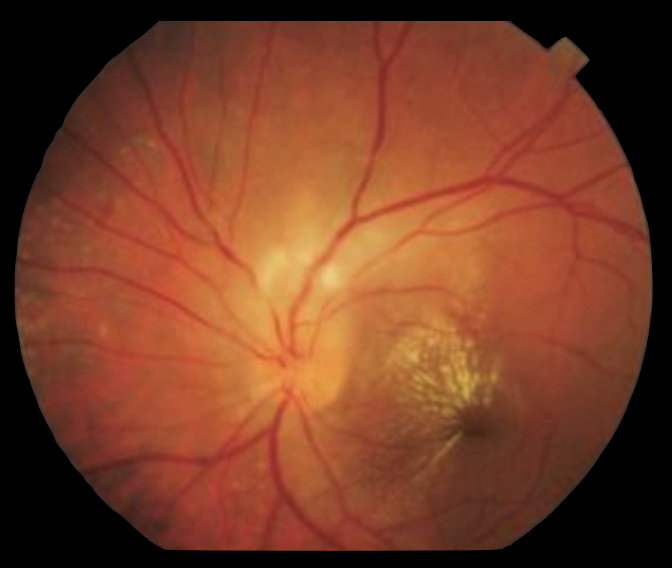

Quais as características da neurorretinite?

Nervo óptico inflamado (papilite) + exsudação macular (estrela macular)

Verdadeiro ou Falso?

A estrela macular da neurorretinite é uma alteração precoce que se resolve rapidamente?

Falso!

A estrela macular pode demorar alguns dias para se formar. A resolução dos exsudatos pode demorar meses para acontecer.